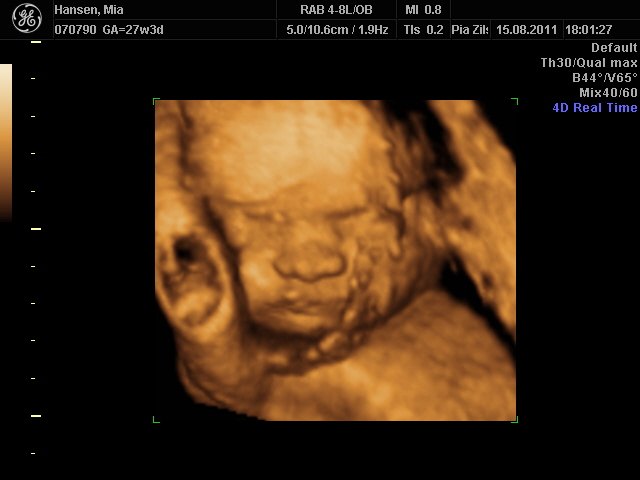

Fantastisk oplevelse. Lillepigen er bare så fin  en rigtig putte-pige

her kommer lidt billeder

Mia 27+3